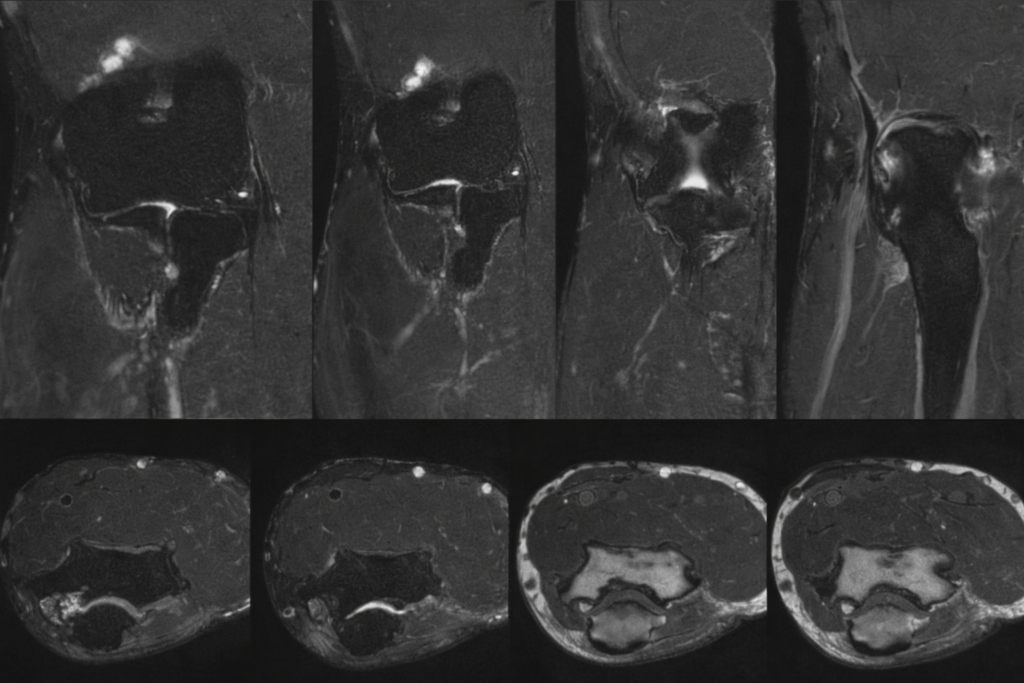

- Exames de imagem: USG ou RM